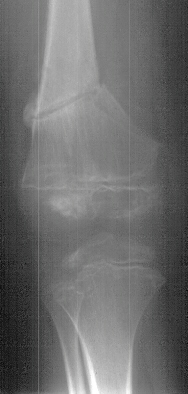

An 11 year old white male presented with a diagnosis of Multiple Epiphyseal Dysplasia (MED). Initially he presented with x-rays revealing mild genu valgum (image1) which progressed (image2) such that he required surgery. He had a supracondylar osteotomy which was performed in 1993 for genu valgum(image3). Two years later he was last seen for low back pain.